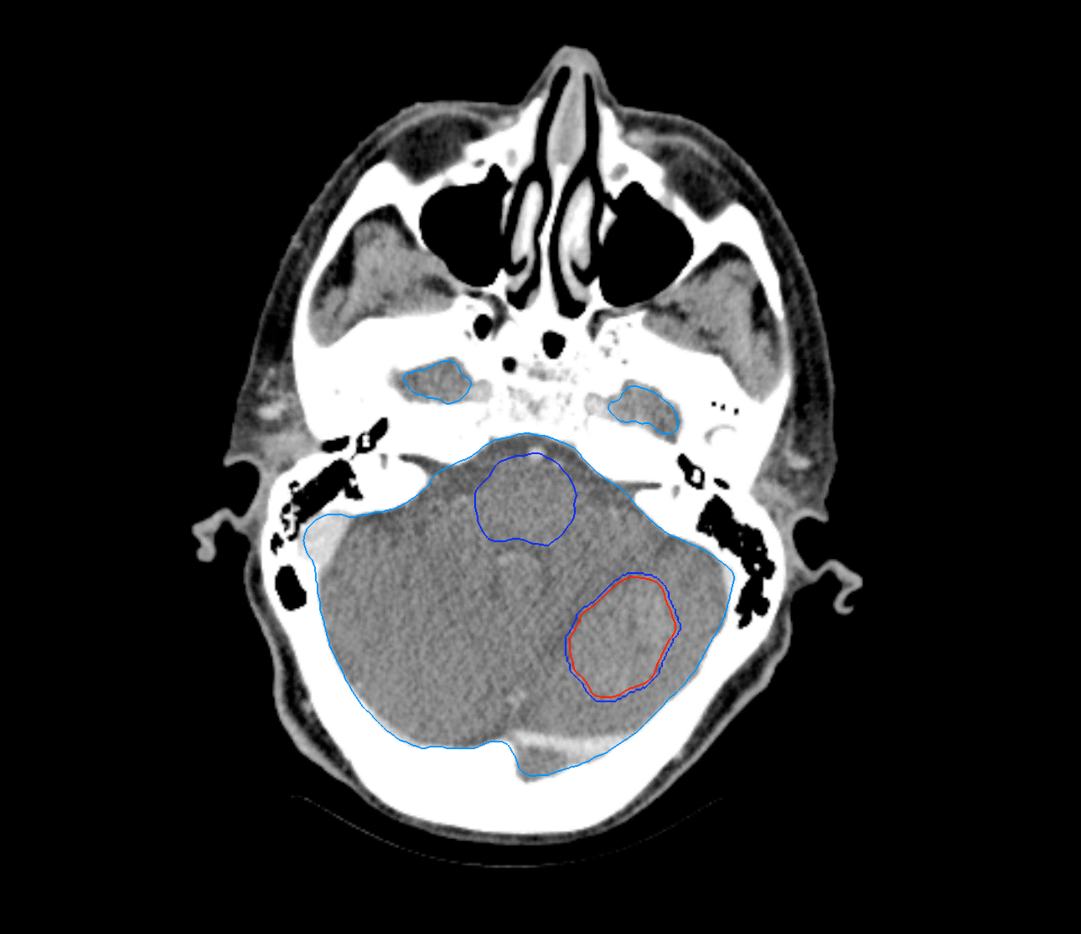

Right Central Lung Metastasis

< View All Plan Studies CYBERKNIFE SYSTEM Right Central Lung Metastasis Case History AGE: 62-year-oldGENDER: Male Medical History Chronic obstructive pulmonary disease (COPD), previous surgery on right lung Chest CT: Suspicious lesion in the right lower lobe PET-CT: hypermetabolic nodule, 3.1cm no evidence of regional or distant metastasis Non-Small Cell